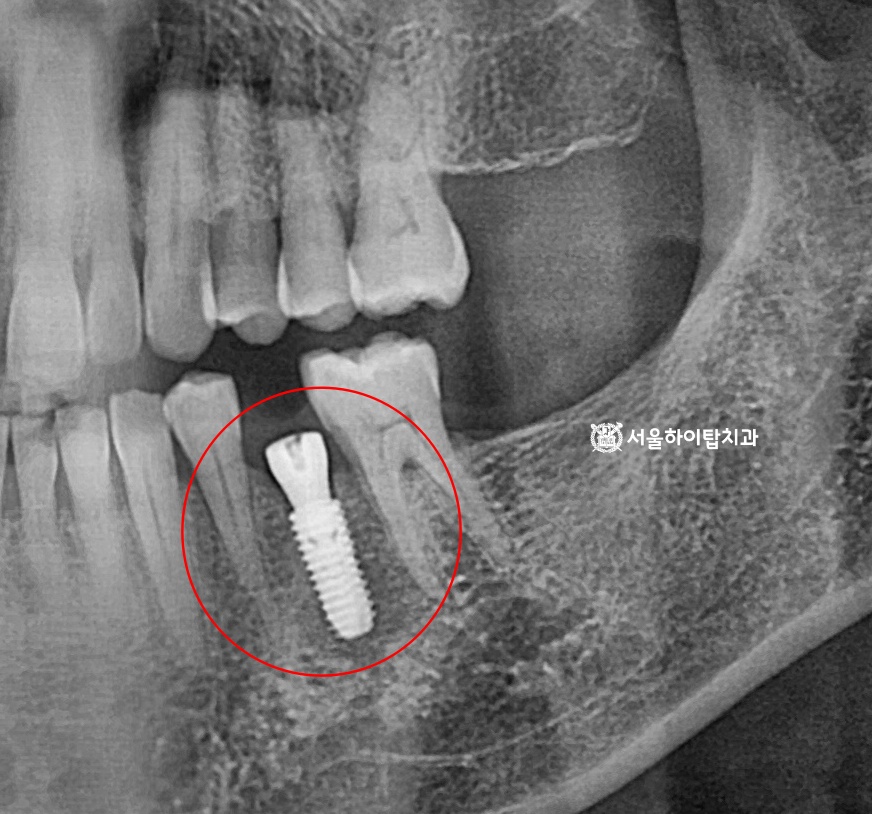

임플란트 식립 진행 과정

앞선 CT 기반 가상 시뮬레이션을 통해 계획한 대로

임플란트가 해부학적으로 안정적인 위치에 식립된 모습입니다.

식립 후 약 한 달 뒤에는 경과 관찰(Follow-up)을 진행하여

픽스처의 초기 골유착 상태와 주변 연조직 치유 양상을 확인합니다.

간석오거리역 치과 에서는 이 시기에는 동요도 여부, 통증 유무,

방사선 사진을 통한 변연골 변화 등을 종합적으로 평가하게 된다고 말씀드립니다.